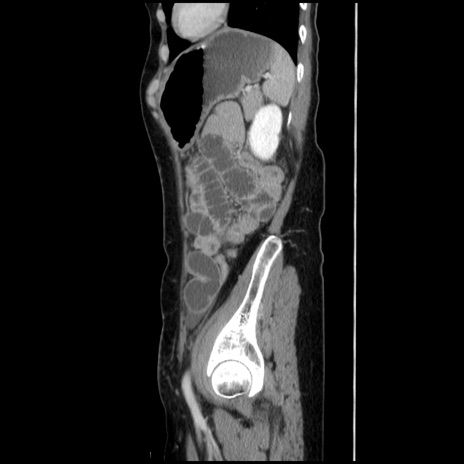

冠状断像

【症例】40歳代 女性

【主訴】上腹部痛、嘔気・嘔吐

【現病歴】約9時間前頃から急に上腹部痛、嘔気、嘔吐が出現。改善しないため救急要請。

【既往歴】子宮頚癌(広汎子宮全摘術、放射線療法)、腸閉塞

【身体所見】腹部:平坦、軟、腸雑音亢進、上腹部を中心に腹部全体に圧痛あり。

【データ】WBC 8400、CRP 0.03